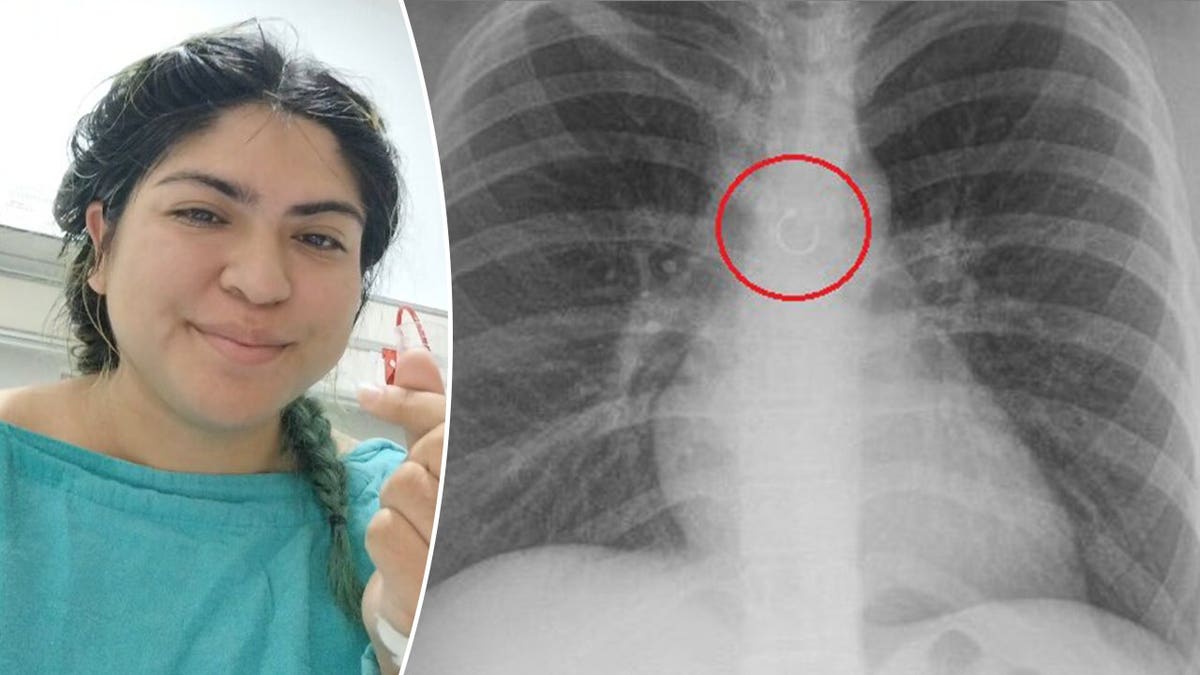

In videos, she shared that the stray accessory sat a mere 0.5 millimeters from her aorta, Jam Press reported.

The nose ring was lodged dangerously close to her aorta, the body’s primary artery. (Jam Press)

If the metal had punctured her lung or heart before doctors discovered it, Deyanira said she likely would have died from a lung collapse or perforated aorta.